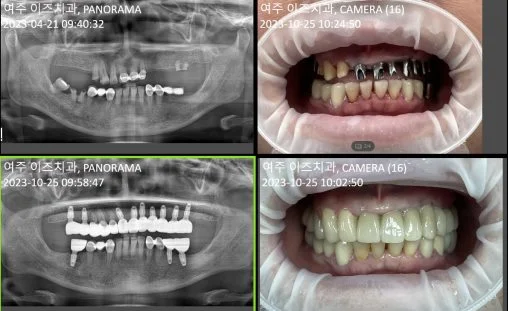

2. 여주이즈치과의원소개

여주이즈치과의원은 경기 여주시 세종로 10에 위치한 치과 진료 서비스 업체입니다. 언제 어디서나 믿을 수 있는 진료 서비스로 유명하며, 최고의 정밀 진료를 위해 첨단 CT(컴퓨터 단층 촬영기)를 완비하고 있습니다. 이를 통해 빠르고 정확한 진단으로 한 번의 마취로 발치와 동시에 당일 임플란트 수술이 가능합니다. 또한, 보험임플란트와 만 65세 이상 보험 틀니도 가능하며, 매복사랑니 발치 역시 안전하게 진행할 수 있습니다. CT로 신경관 위치를 파악하여 어려운 매복사랑니를 발치하는 데 도움을 주고 있으며, 타 치과에서도 많은 의뢰를 받는 대표적인 발치 병원입니다. 궁금한 사항이 있으시면 031-881-2897로 연락해주세요.